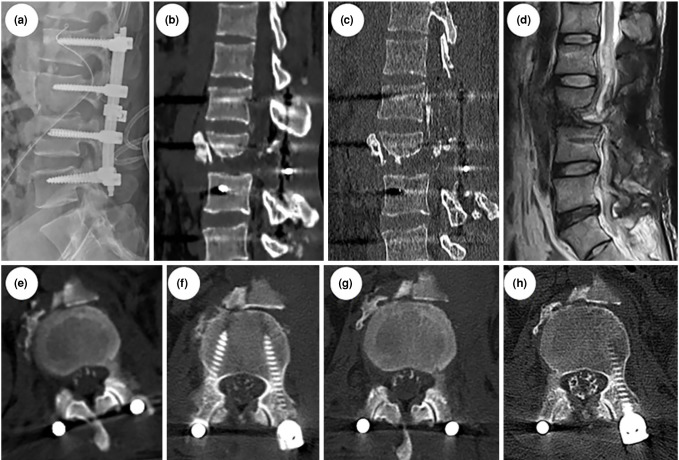

Severe old lumbar fractures and dislocations with associated cauda equina nerve transection are rare clinical presentations which pose significant management challenges. This case report highlights a unique instance of such an injury, emphasizing novel surgical strategies for reconstruction and recovery. A 30-year-old male patient was admitted after sustaining a severe open fracture and degree IV posterior dislocation of L3 vertebra, accompanied by cauda equina nerve transection, spinal cord injury and multiple organ injuries. Following initial stabilization, the patient underwent surgical reduction and internal fixation two months after the injury. The procedure involved cauda equina nerve reconstruction using sural nerve grafts. Postoperatively, the patient showed improved bladder function and regained some mobility. However, he later developed arachnoiditis ossificans of the cauda equina, resulting in severe pain, which required additional surgical intervention. In conclusion, this case underscores the importance of timely intervention in severe thoracolumbar injuries and presents a successful approach to nerve reconstruction.